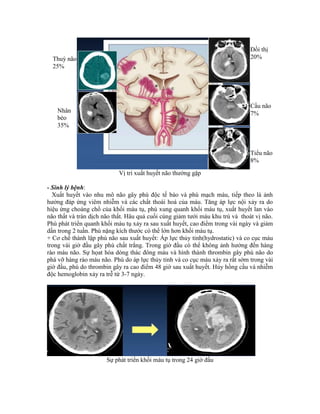

- Sinh lý bệnh:

Xuất huyết vào nhu mô não gây phù độc tế bào và phù mạch máu, tiếp theo là ảnh

hưởng đáp ứng viêm nhiễm và các chất thoái hoá của máu. Tăng áp lực nội xảy ra do

hiệu ứng choáng chổ của khối máu tụ, phù xung quanh khối máu tụ, xuất huyết lan vào

não thất và tràn dịch não thất. Hâu quả cuối cùng giảm tưới máu khu trú và thoát vị não.

Phù phát triển quanh khối máu tụ xảy ra sau xuất huyết, cao điểm trong vài ngày và giảm

dần trong 2 tuần. Phù nặng kích thước có thể lớn hơn khối máu tụ.

+ Cơ chế thành lập phù não sau xuất huyết: Áp lực thủy tỉnh(hydrostatic) và co cục máu

trong vài giờ đầu gây phù chất trắng. Trong giờ đầu có thể không ảnh hưởng đến hàng

rào máu não. Sự họat hóa dòng thác đông máu và hình thành thrombin gây phù não do

phá vỡ hàng rào máu não. Phù do áp lực thủy tỉnh và co cục máu xảy ra rất sớm trong vài

giờ đầu, phù do thrombin gây ra cao điểm 48 giờ sau xuất huyết. Hủy hồng cầu và nhiễm

độc hemoglobin xảy ra trễ từ 3-7 ngày.

Sự phát triển khối máu tụ trong 24 giờ đầu

Thuỳ não

25%

Nhân

bèo

35%

Đồi thị

20%

Cầu não

7%

Tiểu não

8%

+ Sự lan rộng khối máu tụ: 72% khối máu tụ phát triển trong 24 giờ đầu, 38% tăng thể